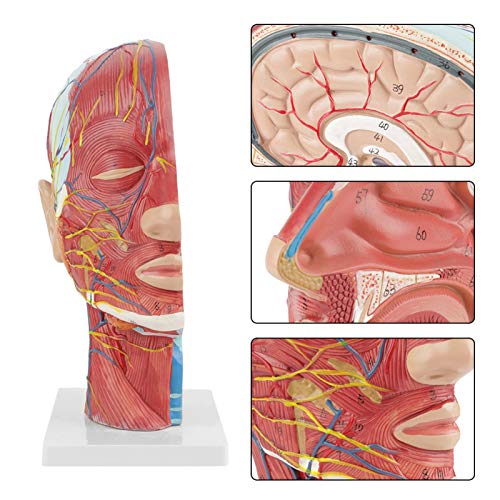

Rode lijn: Artery

Blauwe lijn: Ader

Gele lijn: Zenuw

De ene kant is voorzien van interne anatomie, de andere toont spier- en vasculaire anatomie. Zeer gedetailleerde getallen gemarkeerd, verdiepen het begrip van de structuur van de menselijke hersenen, vasculaire structuren. De gehele structuur is stevig gemonteerd op een kunststof basis, gemakkelijk te observeren. Het model is gemaakt van PVC-kunststof, dat corrosiebestendig, licht is en een hoge sterkte heeft. Toepasbaar op scholen, ziekenhuis, lichamelijke gezondheidsonderwijs, kan als leerhulpmiddel worden gebruikt.